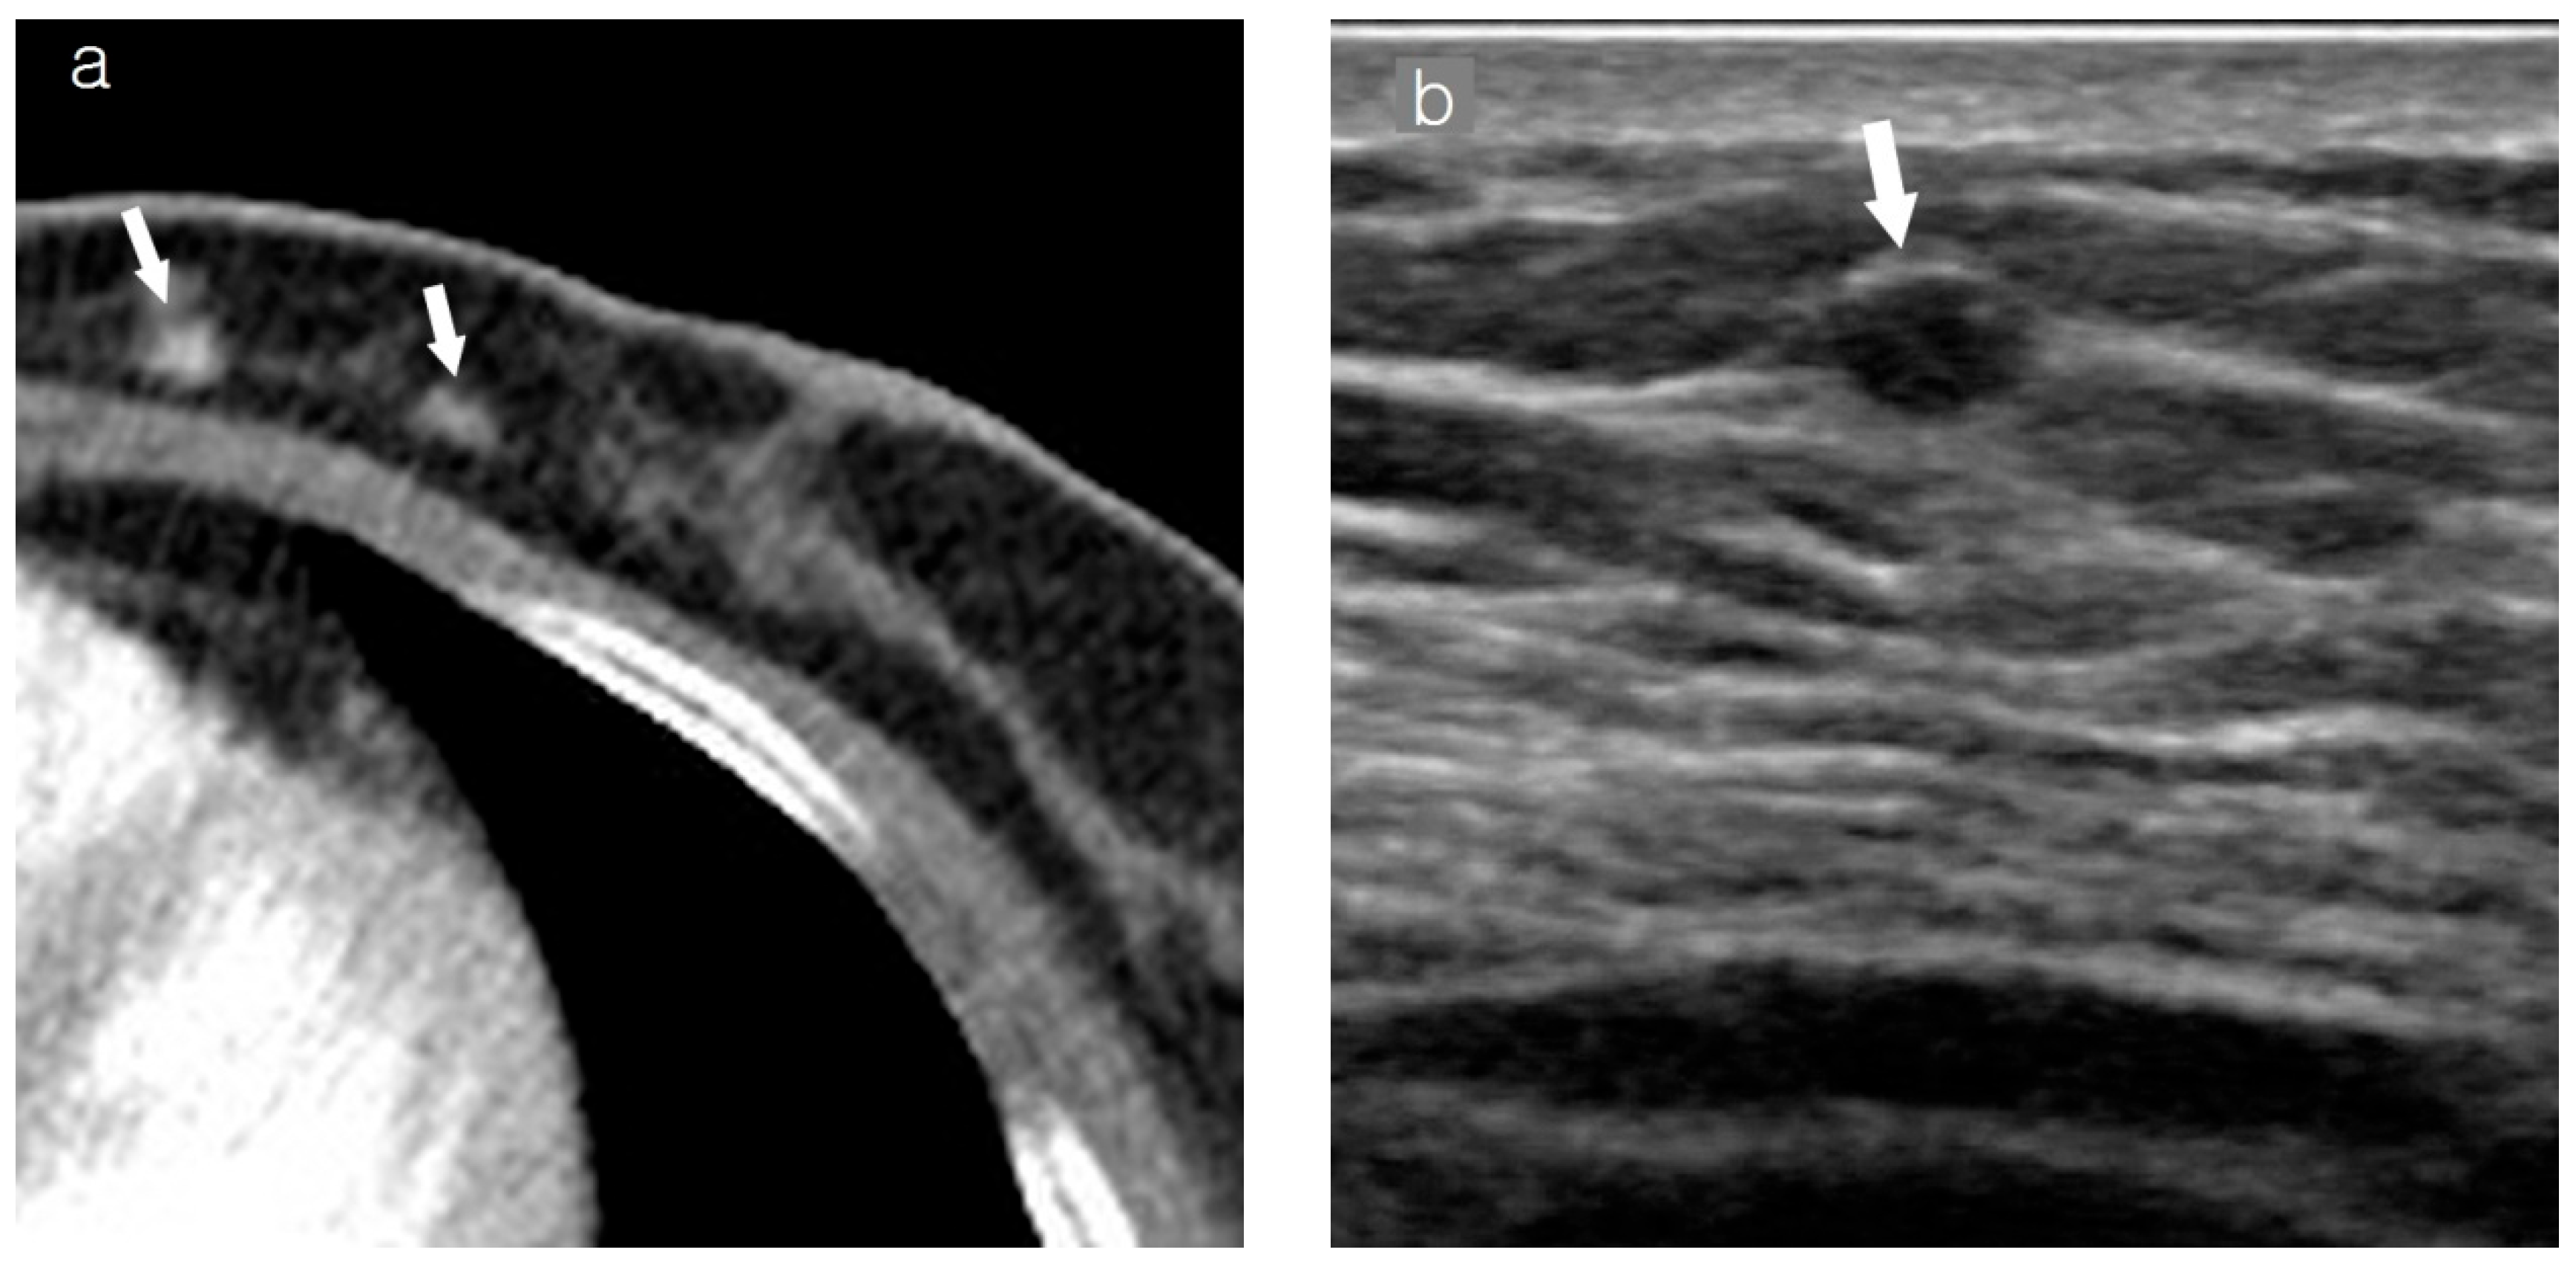

2.3. Assessment of Breast Cancer on Chest CT

2.4. Imaging Analysis